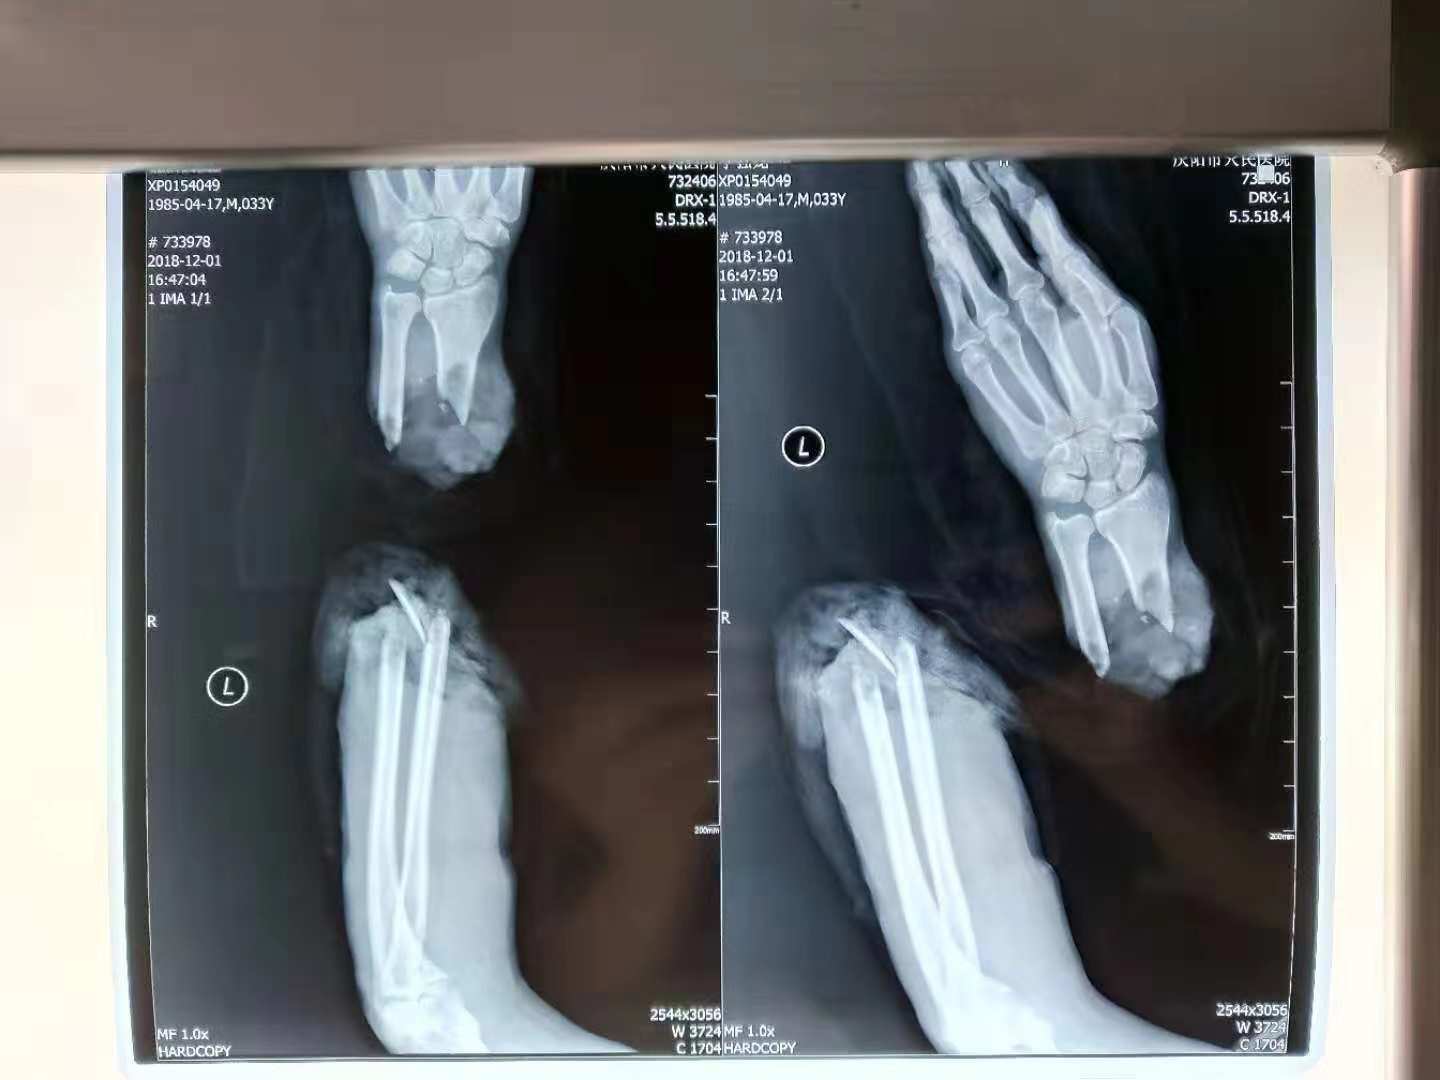

市人民医院手足显微外科急诊收住一名患者,李某某(化名),男,33岁,干活时不慎被电锯伤及左前臂致伤口远端完全离断,急诊以“左前臂完全断离伤” 入院。

面对家属和患者惊恐、慌乱、焦灼、期盼的眼神,面对这种高能量损伤的特殊急诊患者,科室高度重视,迅速成立急诊手术小组。手足显微外科主任张利清带领值班医生高彦龙等手术团队成员争分夺秒,迅速评估患者生命体征、全身情况及患者残端及断肢情况,明确患者有再植手术指征,与患者充分沟通并征得同意后,立即完善术前相关检查,联系手术室及麻醉科做好相关手术准备。很快,手术用的卫材与消毒钢板到位,手术室人员与麻醉准备就位。下午6时,手术正式开始,手术室的无影灯安静而又温暖,断肢再植手术第一步——清创,对断端及残端进行彻底清创,紧接着复位桡骨骨折并直型7孔骨折锁定板对位固定,复位尺骨骨折并克氏针骨髓腔对位固定,经确定对位对线良好,内固定可靠,“骨架子”稳固,开始修复、缝合旋前方肌等前臂掌侧深层肌肉群,为下一步显微镜下吻合血管、吻合神经及肌腱铺设良好的血管床,平实摧毁的“路基”,再造断肢成活的适宜“土壤”。

断肢再植术,每隔1小时需要松解患肢止血带15分钟,以保证患肢血运。15分钟间隔间隙,术者趁机可以松动松动坚硬的颈项,眨巴眨巴眼睛缓解视疲劳,闭目养神稍作休息后继续投入工作。经过团队的坚韧努力,手术历时近11个小时,成功吻合断肢血管6根、神经3根、肌腱25根,将完全断离身体的左前臂再植成功。患者术后第10天,平稳度过24—48小时血管危象,顺利度过7天坏死危险期,现患者生命体征平稳,情绪稳定,患肢血运良好,皮肤颜色温度正常,再植的左前臂无肿胀,五指分别能做轻微屈伸活动。